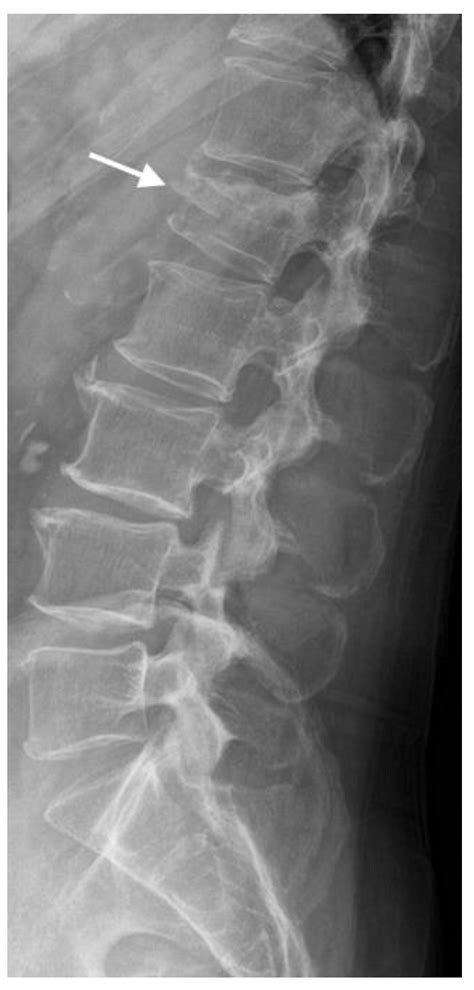

• Imaging Tests: X-rays are the primary tool for diagnosing fractures. In some cases, CT scans or MRIs may be used for more detailed images.

Imaging tests are crucial for understanding the acute fracture meaning and planning the appropriate treatment. X-rays provide clear images of the bone structure, helping to identify the type and severity of the fracture.